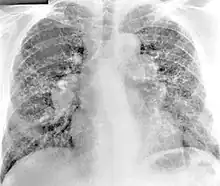

Diagnosis of berylliosis is based on history of beryllium exposures, documented beryllium sensitivity, and granulomatous inflammation on lung biopsy. Given the invasive nature of a lung biopsy, diagnosis can also be based on clinical history consistent with berylliosis, abnormal chest x-ray or CT scan findings, and abnormalities in pulmonary function tests.[16]

The radiologic and pathologic features of berylliosis are very similar to sarcoidosis. Due to the strong clinical and histopathological resemblance of sarcoidosis and berylliosis, patients are sometimes misdiagnosed with sarcoidosis until the history of exposure to beryllium is elicited and beryllium hypersensitivity demonstrated with specific testing. Some studies suggest that up to 6% of all cases of sarcoidosis are actually berylliosis.[17] [18]

Chest radiography findings of berylliosis are non-specific. Early in the disease radiography findings are usually normal. In later stages interstitial fibrosis, pleural irregularities, hilar lymphadenopathy and ground-glass opacities have been reported.[20][21] Findings on CT are also not specific to berylliosis. Findings that are common in CT scans of people with berylliosis include parenchymal nodules in early stages. One study found that ground-glass opacities were more commonly seen on CT scan in berylliosis than in sarcoidosis. In later stages hilar lymphadenopathy, interstitial pulmonary fibrosis and pleural thickening.[21]